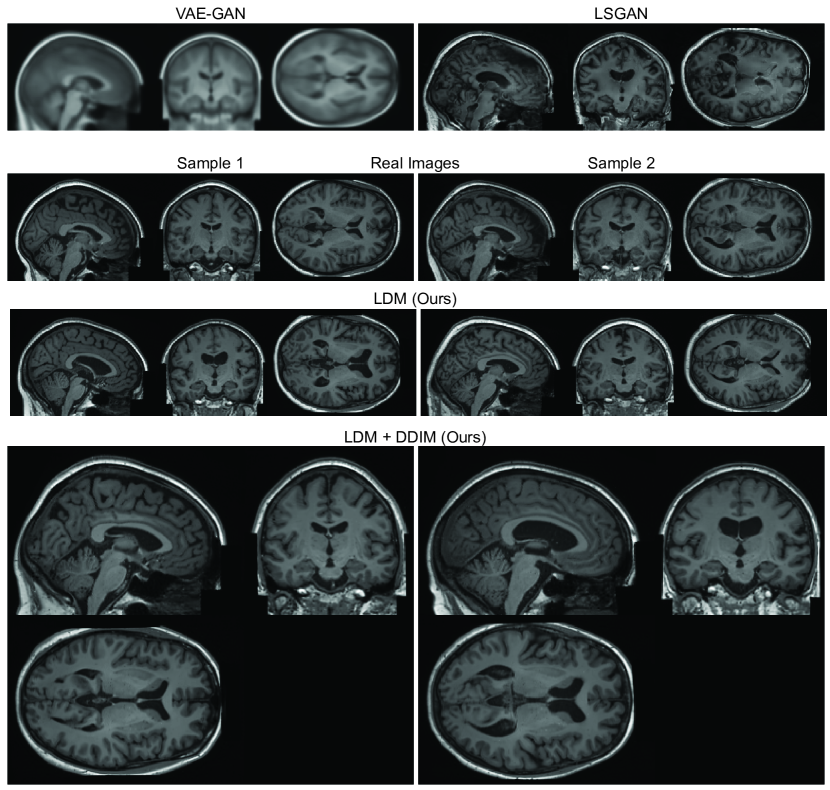

Refer to caption

Figure 1: Real and synthetic samples of head MRI generated using VAE-GAN, LSGAN, LDM and LDM+DDIM.

Fig. 1 shows images generated using LDMs compared to real images and the baselines (i.e., VAE-GAN [18] and LSGAN [21]). Unlike the baselines, we observe that the LDMs were able to sample high-quality images with sharp details and realistic textures. Besides that, training the diffusion models at such a high resolution was much more stable and easier to achieve convergence when compared to the GAN-based baselines. The baselines required a meticulous design of the interaction between discriminator and generator, and they presented problems of mode collapse, showcasing the problems of GAN-based applied in such high-resolution 3D images. Therefore, we will refine and expand our comparisons with other baselines in future works.